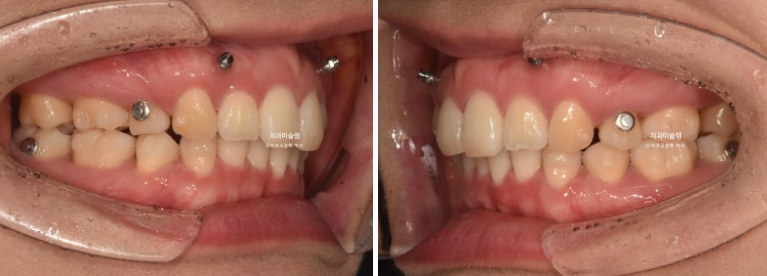

돌출입 교정을 위해 멀리 지방에서 오신 환자분입니다.

윗니 돌출이 심합니다.

아랫니 기준으로 약 1센치가 더 튀어나와 있습니다.

아래 치열은 덧니가 심한 상황입니다.

골격분석 결과 심한 상악골 전방 돌출을 동반한 골격성 2급 부정교합 입니다.

상악골 과잉에 의한 돌출은 돌출입 교정 중에서도 난이도가 높습니다.

상악과 하악의 골격 부조화가 심해 아래턱이 상대적으로 뒤로 밀려있는 상태여서 위 앞니 각도를 이상적으로 유지하기가 쉽지 않습니다.

입이 안 다물어질 정도의 윗니 돌출과 심한 아래 덧니를 해결하려면 작은어금니 4개 발치는 불가피합니다.